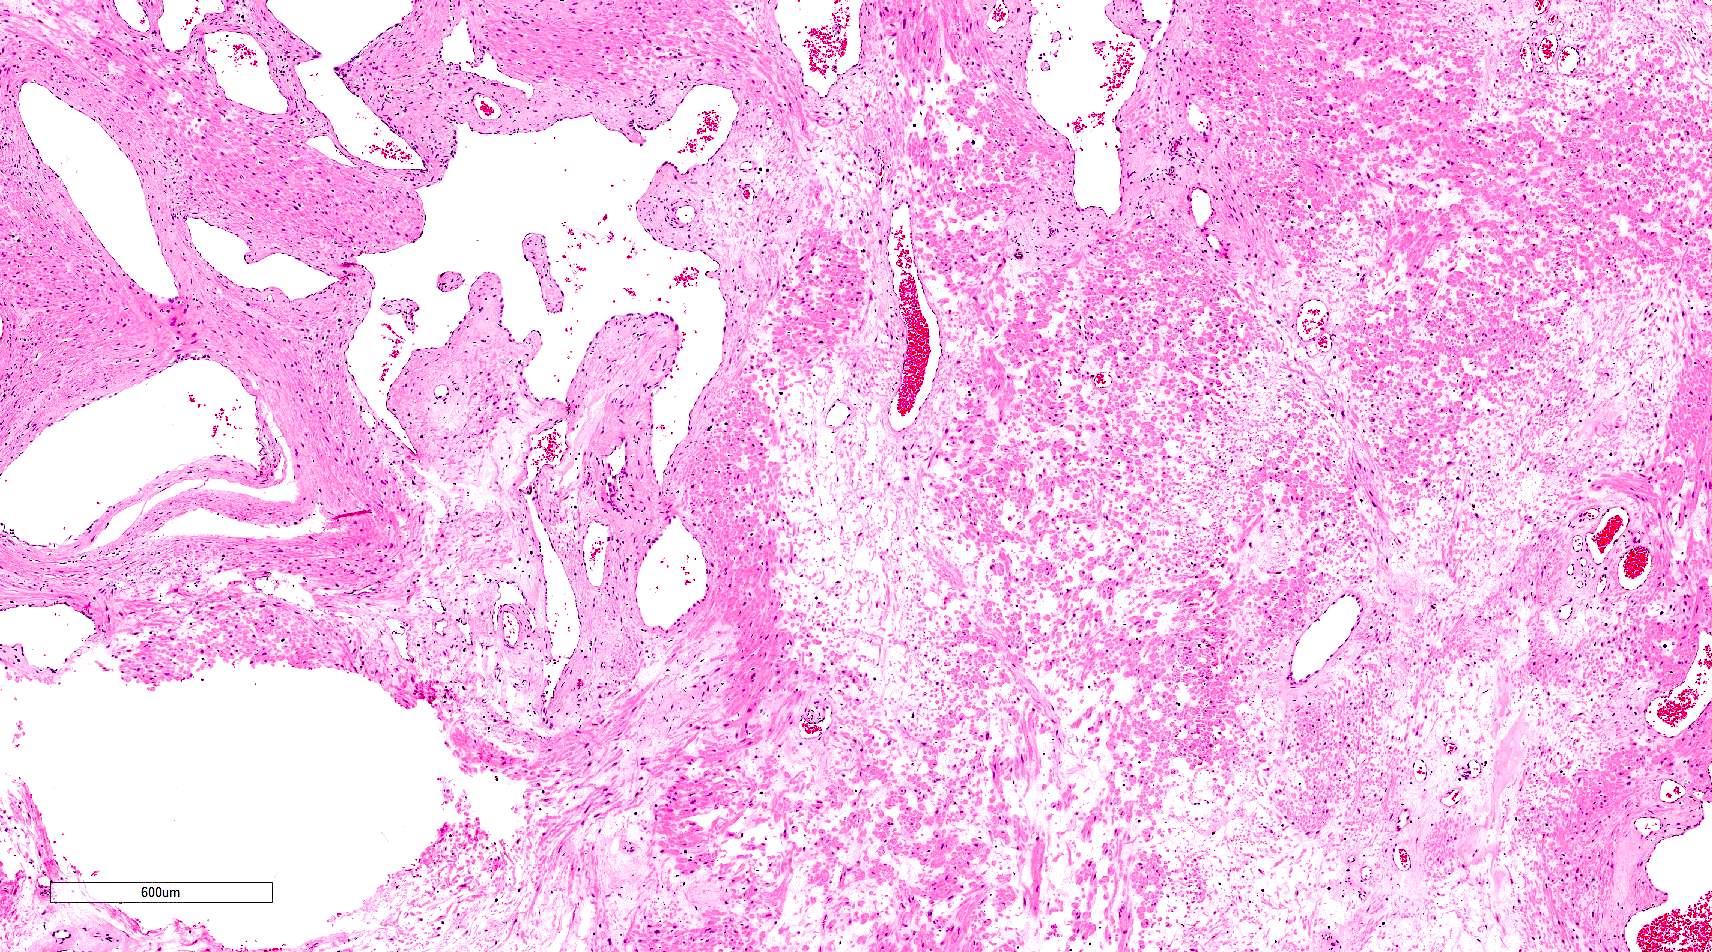

Microscopic (histologic) description

- Encapsulated proliferation of eosinophilic smooth muscle cells with minimal nuclear pleomorphism

- Rounded or slit-like veins with muscular walls present within the tumor (J Cutan Pathol 2017;44:342)

- Tumors can further be classified into 3 subcategories, first described by Morimoto et al:

- Cavernous type: dilated vascular channels, the walls of which are difficult to distinguish from the intervascular smooth muscle

- Calcification and marked degeneration, including hyalinization and myxoid changes, may be present (J Cutan Pathol 2017;44:342, J Ultrasound Med 2019;38:1201)

Microscopic (histologic) images

Contributed by Ohoud Aljarbou, M.D., Jijgee Munkhdelger, M.D., Ph.D. and Andrey Bychkov, M.D., Ph.D.